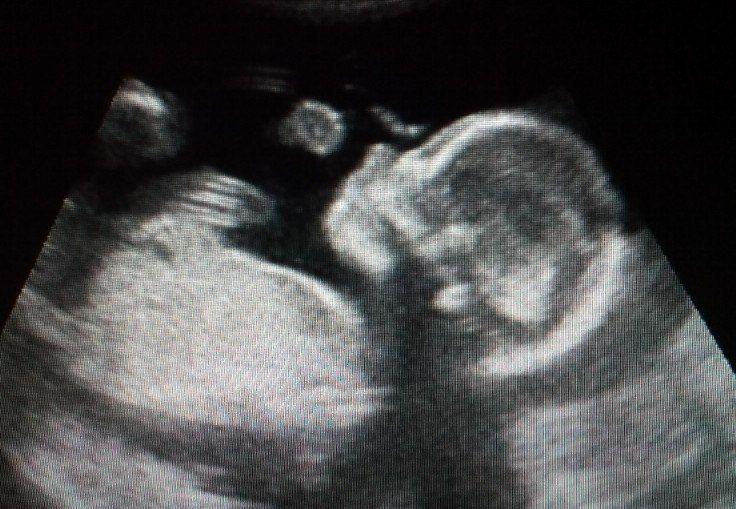

Пришли в родзал, врач посмотрел раскрытие, вскрыл мне пузырь и сразу перевели на родильное место. Доктор спросил, какой вес плода по УЗИ, я ответила, что 3900+- 10г. На что он только засмеялся "откуда в таком маленьком животе 3900 может быть?". (Живот у меня при всех беременностях был небольшим, да и мой вес до беременности 43кг при росте 172.